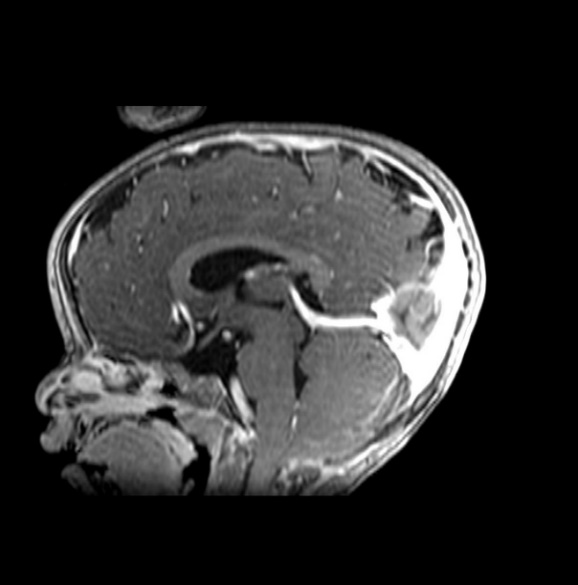

MRI findings showed the lack of the normal flow void of the left internal carotid canal and the first part of the left middle cerebral artery (Figures 1 and 2). The pituitary gland is flat. No evident anterior or posterior pituitary gland tissue or pituitary stalk is observed. The pituitary gland's strong posterior signal is not detected in situ or

ectopic. The left medial cerebral artery originates within the posterior circulation, and the left internal carotid artery cannot be seen. No intra, supra, retro or parasellar masses. Normal MRI appearance of the optic chiasm and corpus callosum. Otherwise, normal MR appearance of the brain parenchyma with no definite focal lesions. Diagnosis of congenital panhypopituitarism associated with agenesis of ICA was made.

a)

b)

c)

d)

Figure 2. a-c) show coronal MRI brain images, and d) is a view in which the left midcranial artery is coming from the posterior circulation and the left internal carotid artery is not visible (agenesis).